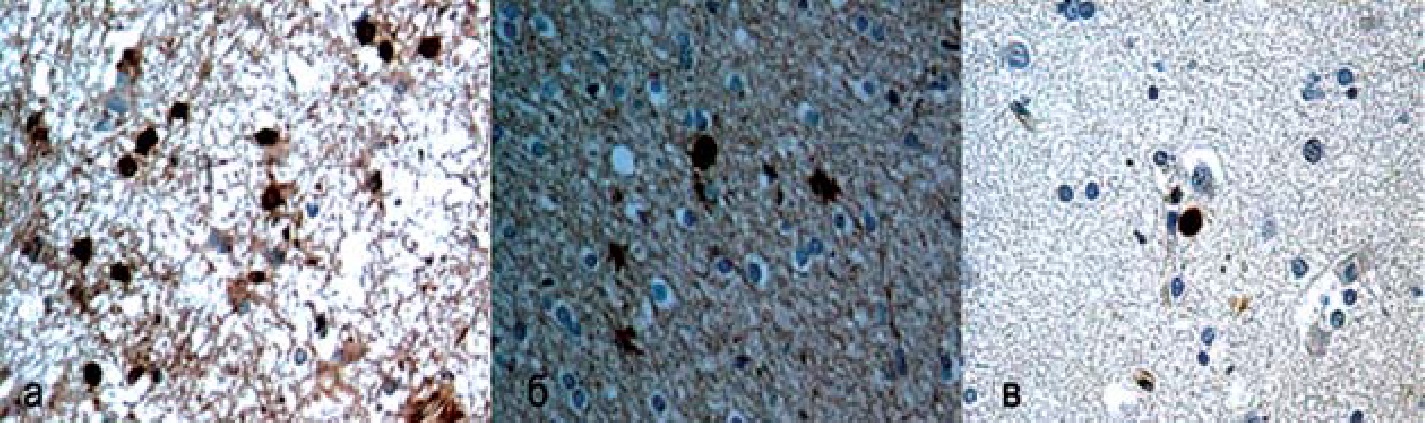

При иммуногистохимическом исследовании были выявлены активация нейрогенеза и аксоногенеза. Часть установленных изменений не противоречила данным литературы [8, 20]. Имела место активация «канонического» нейрогенеза на стороне поражения (у человека и животных), единичность выявляемых новообразованных клеток (у человека и животных), а также сам факт их выявления в разных областях мозга (у животных). Однако выявленные нами изменения были установлены впервые. Прогениторные, стволовые (Musashi1+Nestin+) и пролиферирующие клетки (PCNA+, Кi67+) обнаружены в образцах только из тех областей мозга, где имелось улучшение функционального состояния (клинически, по данным позитронно-эмиссионной томографии) и отсутствовали явные структурные повреждения (по данным магнит- но-резонансной томографии, морфологически), рис. 4. Постмитотические нейроны с инициицированным аксональным ростом (TUC4+) и постмитотические зрелые нейроны (NeuN+), напротив, определялись во всех областях. Исключение составило мозолистое тело: в нем, как и в здоровом взрослом мозге, NeuN+-клеток не было, но имелись TUC4+-клетки, причем их число было максимальным (16) по сравнению с остальными образцами. Этот факт не только подтверждал нейрогенез, но и свидетельствовал о «вновь открывшемся» потоке миграции новообразованных нейронов в лобные доли мозга, поскольку аналогичный поток описан только у детей до 1,5 лет [23].

Рис. 4. Иммуногистохимическое исследование головного мозга на этапе восстановления сознания после двух курсов МПБТ. Реагент+-клетки окрашены коричневым, ув. ×320: а − TUC4+-клетки в мозолистом теле; б − TUC4+-клетки с видимыми нейритами в передней поясной извилине; в − Nestin+-клетка в середней поясной извилине

Не исключено, что причиной «восстановления» потока миграции новообразованных нейронов по- служили структурные повреждения в мозолистом теле, однако они не были установлены при макро- и микроскопическом исследовании. Более вероятно, что «восстановление потока» было связано с восстановлением функциональной активности передних отделов поясной извилины (структурных повреждений в этой области также не выявлено). Как известно, последняя играет важную роль в восстановлении осознанности [24], и именно в ней имелось максимальное количество разных определяемых новообразованных клеток, клеток с инициированным нейритным ростом и видимыми нейритами. В среднем мозге было установлено максимальное число Кi67+-клеток, что может предположительно соотноситься с постепенным регрессом сонливости.

Поскольку прогениторные, стволовые и пролиферирующие клетки не обязательно будут дифференцированы в нейроны, а нейритный рост может проявиться и в зрелых нейронах, факт наличия TUC4+-клеток в мозолистом теле подтверждает факт нейрогенеза и его функциональность. Следовательно, при восстановлении сознания имеет место и структурно-функциональная репарация мозга. Единичные прогениторные, стволовые и пролиферирующие клетки, если они появляются в зоне структурного повреждения, имеют сомнительное значение, но в областях, имеющих функциональные нарушения в отсутствие структурных повреждений, единичные клетки могут играть весьма существенную роль. При этом отсутствие эпилептической активности исключает аберрантный нейрогенез [20]. Инициация аксонального роста, очевидно, отражает процесс восстановления межнейронных связей и взаимодействий [7]. Поскольку экспериментальные исследования на лабораторных животных не применимы при изучении восстановления сознания человека, роль МПБТ (а также других препаратов) в структурной репарации мозга при улучшении сознания пока может только обсуждаться.